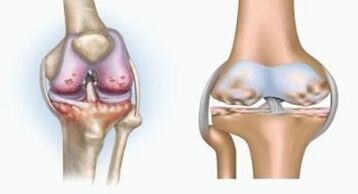

Both pathologies influence the joints, but differ in the nature of the changes.

With arthritis

Arthritis is an inflammation of the connective tissue - a synovial membrane that contains many vessels and provides lymphatic flow.The inflammatory process leads to a violation of the nutrition of joint tissues, due to which the production of joint lubrication - synovial fluid is limited.

With arthrosis

Arthosis is a degenerative dystrophic process associated with the destruction of the cartilage tissue of the joint.The cartilage is gradually destroyed, dry, the distance between the bones of the joint decreases, which is the cause of the pain.In serious forms, destruction affects the bones.They become more porous, they lose density, become fragile.